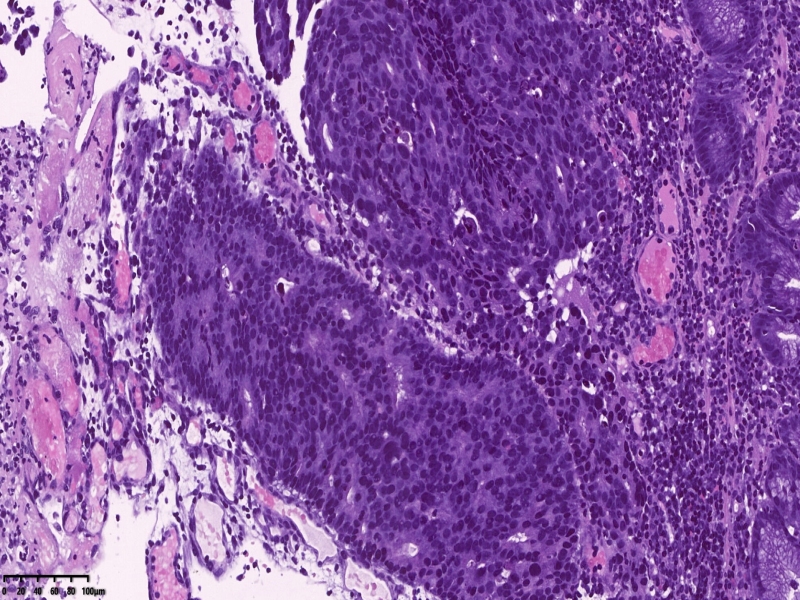

镜下所见:胃粘膜组织数块,炎症背景,其中3块固有层内可见细胞团,瘤细胞排列呈条索状迂回后呈巢状,巢的边缘瘤细胞呈栅栏状。细胞形态似柱状。

第一感觉考虑神经内分泌肿瘤?会诊考虑低分化腺癌。以前也遇到一个类似病例,贲门口占位,初步考虑神经内分泌肿瘤,但是神经内分泌标记均为阴性,最后考虑低分化腺癌。

免疫组化:ki67增值指数较高约80%,CK7VillinCAM5.2、CEA+,CA19-9CDX-2部分+